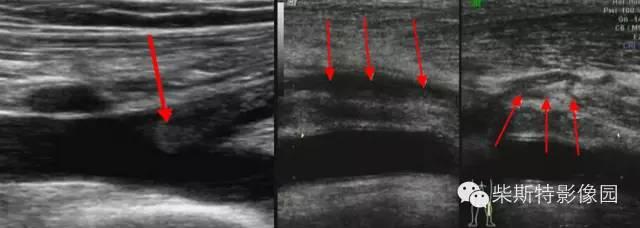

下肢深静脉超声

下肢深静脉超声:红色箭头所指为血栓(纵切面)

下肢深静脉彩色多普勒CDFI:红色箭头所指为血栓(纵切面)